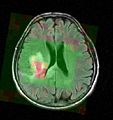

We verified the registration of the spectroscopic images, now allowing to jointly visualize parametric maps (i.e., metabolic maps) of the MRSI signal processing module together with morphological images in Slicer (see Figure 1 below).

thumpnail

Figure 1 - 3D parametric map showing the NAA amplitudes of the spectra in a MR spectroscopic image in Slicer.